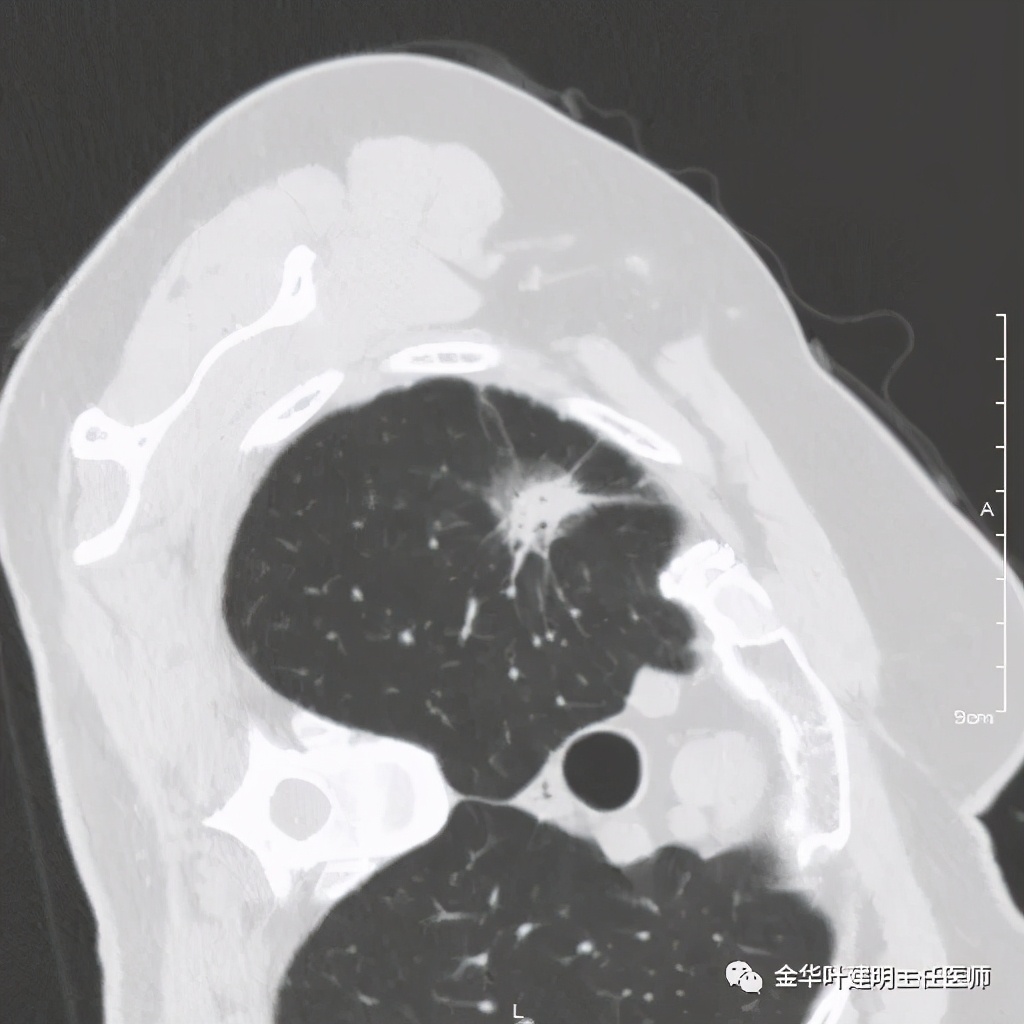

四、浸润性腺癌贴壁伴恶性度较高的实性成分:

影像特征:浸润性腺癌的贴壁生长型若伴有乳头、微乳头、实体型等成份时,更是典型的恶性的特征。此例是贴壁占60%,乳头成分占40%。我们来看其特点:桔色箭头示磨玻璃成分(代表贴壁生长部分),中央是实性成分(代表乳头生长部分),而且实性部分有收缩力(病灶向中间拉的趋势),密度高的部分又其内部密度不大均匀,毛刺也是长短不一。也就是说: 混合磨玻璃结节伴实性部分的收缩力 是其最显著的特点。实性部分若是实体型,也一般是类似表现。预后情况主要看实性成份的占比及亚型,因为贴壁成分是恶性度不高的,但若位微乳头或实体型,那便预后会差一些。也比腺泡型差。